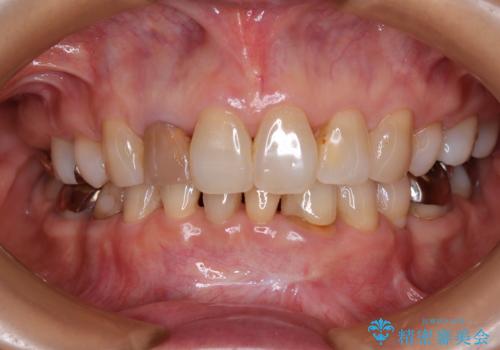

- 奥歯の目立つ銀歯と、神経が失活して変色した前歯を気にして来院された患者様です。

長年口を開ける度に気になっていた銀歯が一気に自然な色合いとなり、患者様には大変満足していただけました。